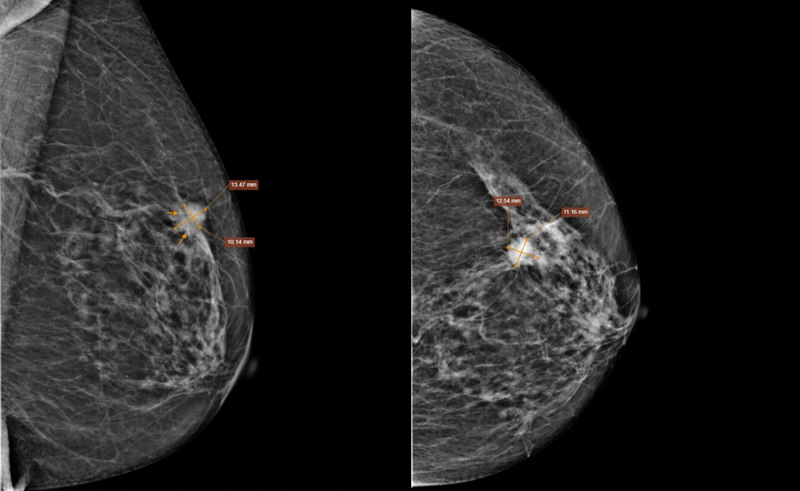

Chụp X-quang tuyến vú kỹ thuật số (Mammography) phát hiện nốt tăng đậm độ nhu mô vú trái, phân loại BIRADS 5.

Chụp X-quang tuyến vú ghi nhận nốt tăng đậm độ nhu mô vú trái, phân loại BIRADS 5